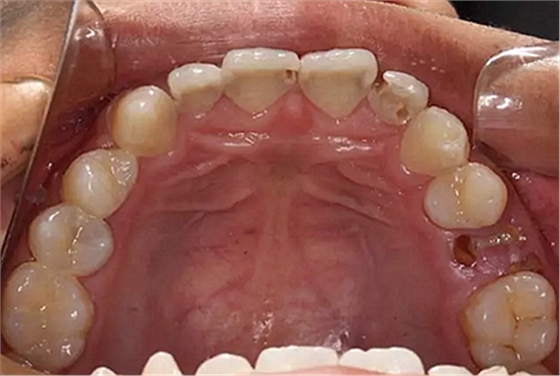

我們的主人今年才25歲,可卻從很小的時候就嗜好喝可樂等碳酸飲料,幾年下來,讓我們兄弟姐妹們整天浸在碳酸里受這蝕骨之痛,原本皎潔的外貌如今早己經(jīng)是腐蝕不堪、丑陋無比,更有甚者,一些兄弟姐妹們已經(jīng)病入膏肓,被病痛折磨奄奄一息。

下面是醫(yī)生眼中和ct下的我們

一身病痛啊

牙結石、牙齦炎癥、牙體殘缺、慢性牙髓炎、蛀牙......

才二八芳華的我們

已經(jīng)滿目蒼夷

再來看看曾經(jīng)的我們